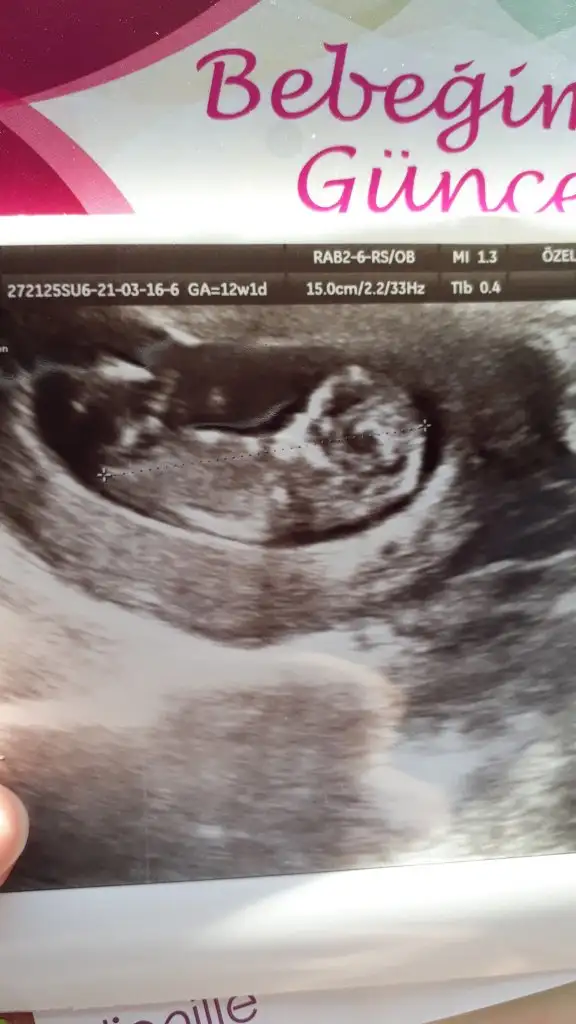

Kızlar tahmin edeniniz varmı yorum yazarsanız çok sevinirim 12. Haftadayiz

Eklentiler

• 20210316_112254.webp

28,5 KB · Görüntüleme: 43